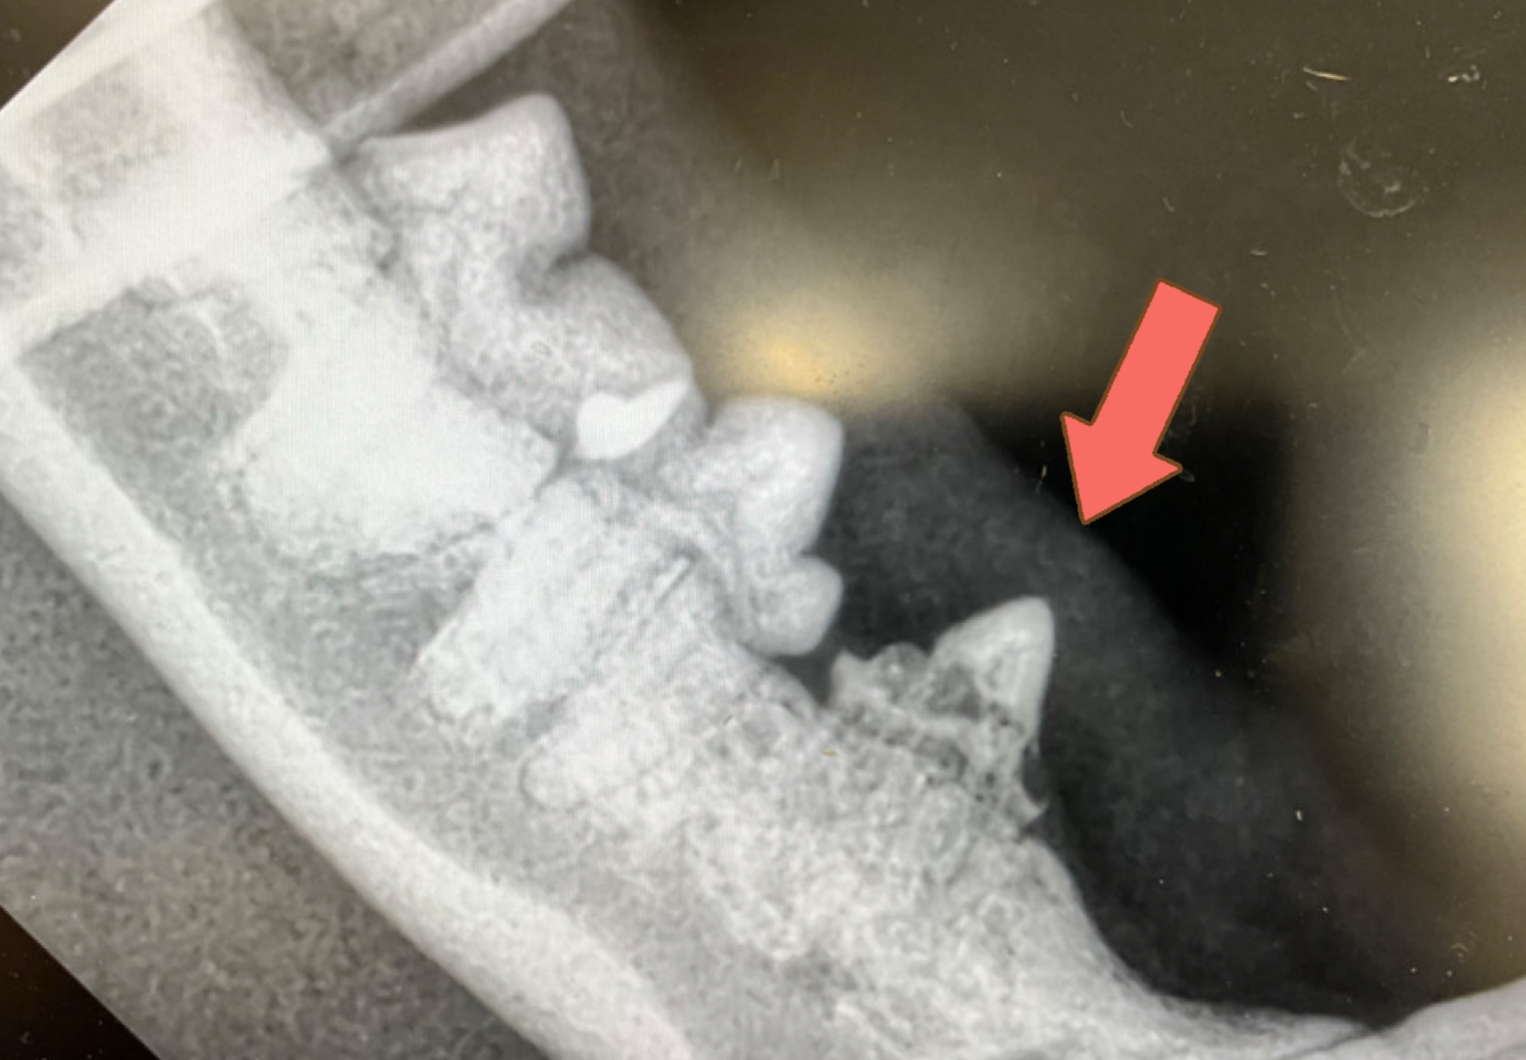

身体検査では、吸収病巣の好発部位でもある左右下顎の第2前臼歯で病変を認めました。

全身麻酔下で歯のレントゲンを撮影すると歯の付け根あたりから歯が溶けたように吸収されて一部骨に置き換わっているのが分かります。